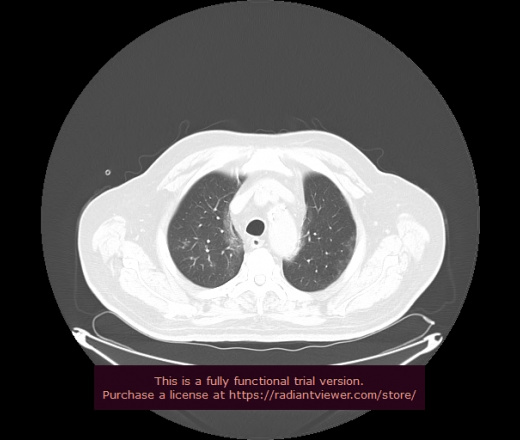

Уважаемые коллеги, если имеется интерес, сможете ли Вы спрогнозировать дальнейшее +-одинаковое течение процесса у 4 данных разных пациентов? Зацепиться где-то можно очень просто, где-то нельзя.